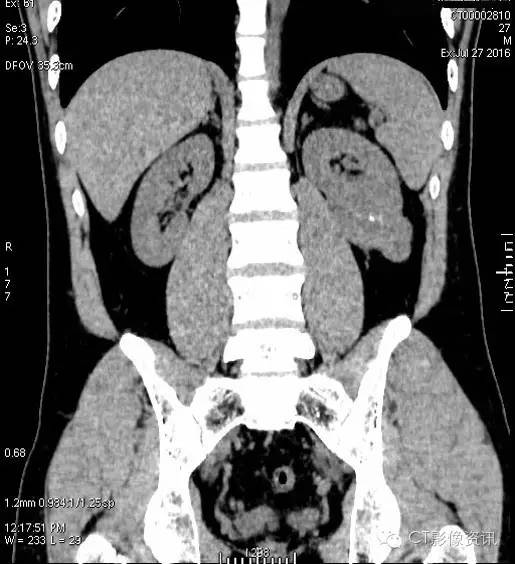

左肾病变位于左肾下极外后侧,与左肾髓质分界不清,向肾外生长并分叶。增强扫描左肾病变强化明显,皮质期病变强化程度低于左肾皮质,与左肾髓质相近,实质期及延迟期强化程度均显著低于左肾实质。

右肾病变位于右肾下极内后方,与肾实质分界清晰。增强扫描右肾病灶轻微强化,强化程度均低于右肾实质。